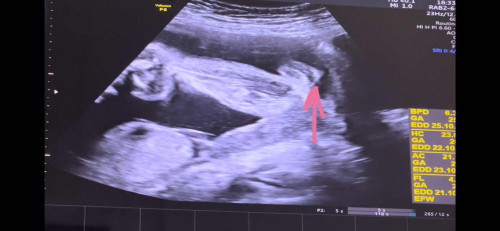

หมอบอกเพศหญิง ชัวร์มากแค่ไหนคะ

เอาภาพอัลตร้าซาวด์มาให้แม่ๆช่วยดูจ้า ซาวด์มาตอน 27w อยากทราบว่าโอกาสผิดพลาดมากน้อยแค่ไหน อยากเห็นภาพอัลตร้าซาวด์เพศหญิงของแม่ๆจังเลยจ้า#ขอบคุณสำหรับคำคอมเม้นล่วงหน้าค่ะ #ขอความคิดเห็นของคุณแม่หน่อยค่ะ #ขอบคุณล่วงหน้าสำหรับความคิดเห็นค่ะ

ดูแล้วก็เห็นกีบเลยนะคะแม่27wแล้วไม่น่าพลาด 😅

ไม่หน้าใช่ไข่ค่ะแม่มาเป็นกีบเลย

บ้านนี้ ลูกสาวเป็นกรีบแบบนี่คะ ถ้าผช จะพุ่งกว่านี้